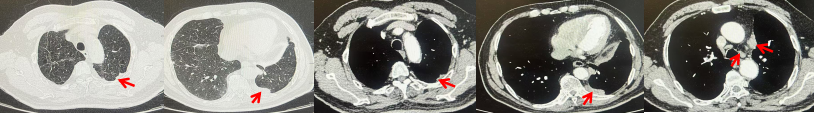

2024.11.19患者出现右侧胸痛,复查胸部CT检查示右侧胸膜肿物,大小约31mmX24mm,右侧4、5肋骨骨质破坏,考虑转移(如图2)。建议患者穿刺活检取病理明确诊断,患者拒绝,经MDT会诊后结合影像学表现及病史考虑为胸膜转移,肋骨转移,分期为rT0N0M1a IVA期,DFS仅仅17个月。2024.12.05起行信迪利单抗联合培美曲塞+卡铂方案治疗4周期,复查胸CT评效PR(如图3)。之后给予信迪利单抗+培美曲塞维持治疗6周期,期间复查CT评效PR(如图3)。目前信迪利单抗+培美曲塞维持治疗中,截止至目前PFS约为8个月,治疗期间未出现明显毒副反应。

图2:患者胸膜及肋骨转移(2024.11)胸部CT肺窗、纵隔窗及骨窗

图3:患者免疫联合化疗治疗后胸部CT,(A、B)图展示信迪利单抗联合培美曲塞+卡铂治疗

4周期(2025.02)疗效,(C、D)图展示信迪利单抗+培美曲塞维持治疗6周期(2025.07)疗效